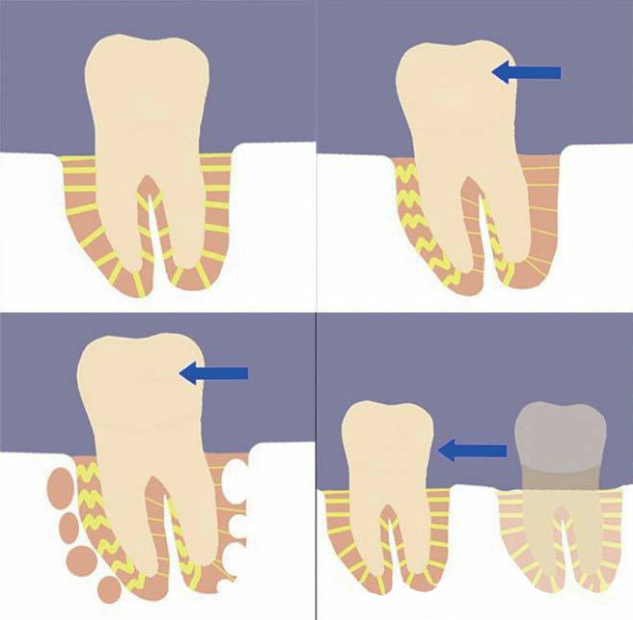

误区2 牙齿矫正后会使牙齿松动

牙齿本身也不可能一辈子待在原地不动,而是处于稳定与移动的平衡中。矫正就是通过外力暂时打破这个平衡,为牙齿搬家。矫正产生的骨改建带来牙齿生理性的移动,在移动过程中暂时有一定程度的松动很正常。当牙齿移动到新的位置上,自然又回归到平衡中,重新稳定下来。

误区11 矫治力越大,牙齿移动越快,矫治力小,不疼,牙齿移动慢或不移动

牙齿移动是骨细胞参与改建的缓慢的生理性移动,不同于宏观世界的物理力学现象,绝非力量越大速度越快。实际上很小的力量即可启动牙齿移动,力量过大反而会移动停止或带来很多副作用。物极必反,矫正不能超越生理限度。矫正期间只要缩短复诊间隔,就诊频繁一些,就能加快进度继而缩短疗程。

牙齿移动是缓慢的生理性移动,平均一个月最多移动1mm。如果因为着急频繁复诊,牙齿和牙周组织失去了休整的时间,就可能带来不可逆的不良后果。牙齿矫正不能拔苗助长,必须尊重生理规律。